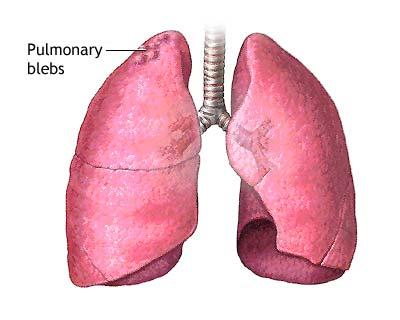

Pneumotoraxul (plamanii colabati)